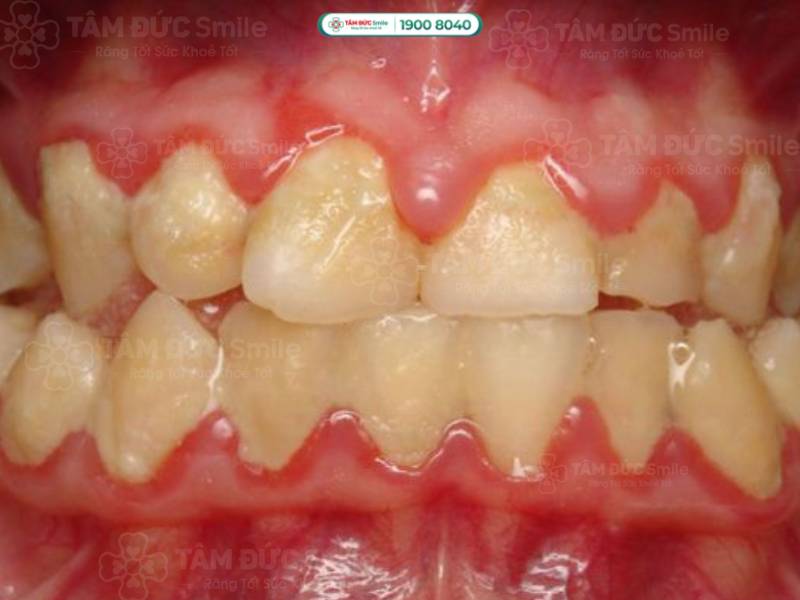

Viêm nướu và viêm nha chu là căn bệnh phổ biến trong các bệnh liên quan đến nhiễm trùng khoang miệng. Viêm nướu được xem là giai đoạn đầu của viêm nha chu với biểu hiện sưng đỏ chân răng, bạn có cảm giác đau rát, tức nặng vùng mặt. Ở giai đoạn sau, viêm nướu tiến triển thành viêm nha chu, thường gây chảy máu chân răng, hôi miệng, tụ mủ và khó khăn khi ăn nhai.

Chân răng bị đỏ và sưng do viêm nha chu